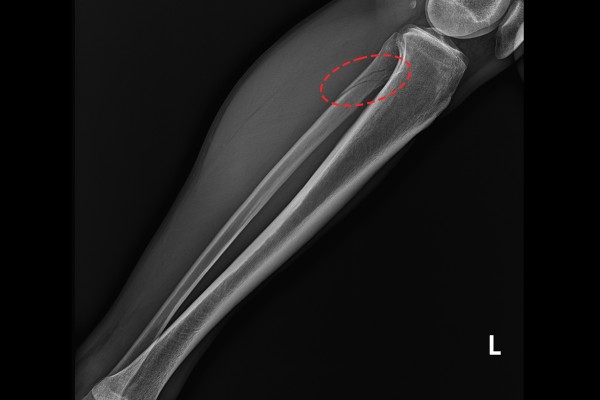

이러한 충격은 위로 전달되어, 근위비골 골절이 함께 발생하는 경우도 흔히 나타납니다. 이렇게 근위 비골이 부러지는 것을 메종뇌브 골절(Maisonneuve Fracture)라 합니다. 환자분 역시 사진을 보시면 메종뇌브 골절이 동반된 것이 확인되어 발목 원위경비결합인대 및 삼각인대 손상, 메종뇌브 골절(Syndesmosis inj(distal T-Fibula) ankle Lt. Deltoid avulsion inj ankle Lt. Fx.prox.fibula knee Lt.(Maisonneuve Fracture))을 진단하였습니다.